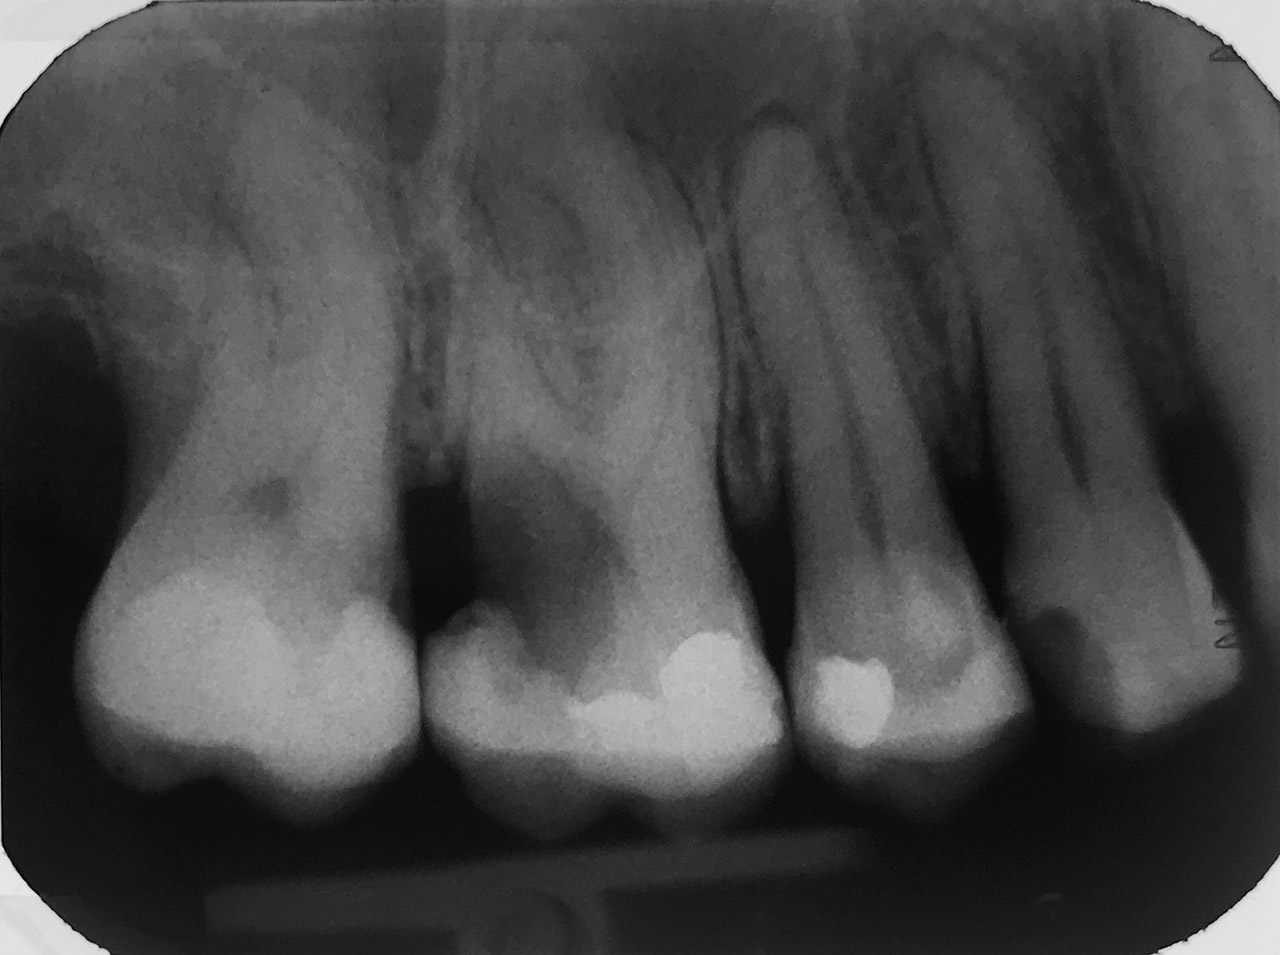

Kariestherapie:

Anamnese: tiefe Karies (Caries profunda) an beiden Oberkiefer 1. Molaren

Therapie: Zahn 16 musste Wurzelbehandelt werden, Zahn 26 konnte vital erhalten werden.

Aufbau beider Zähne in adhäsiv mit Composite/Schichttechnik.